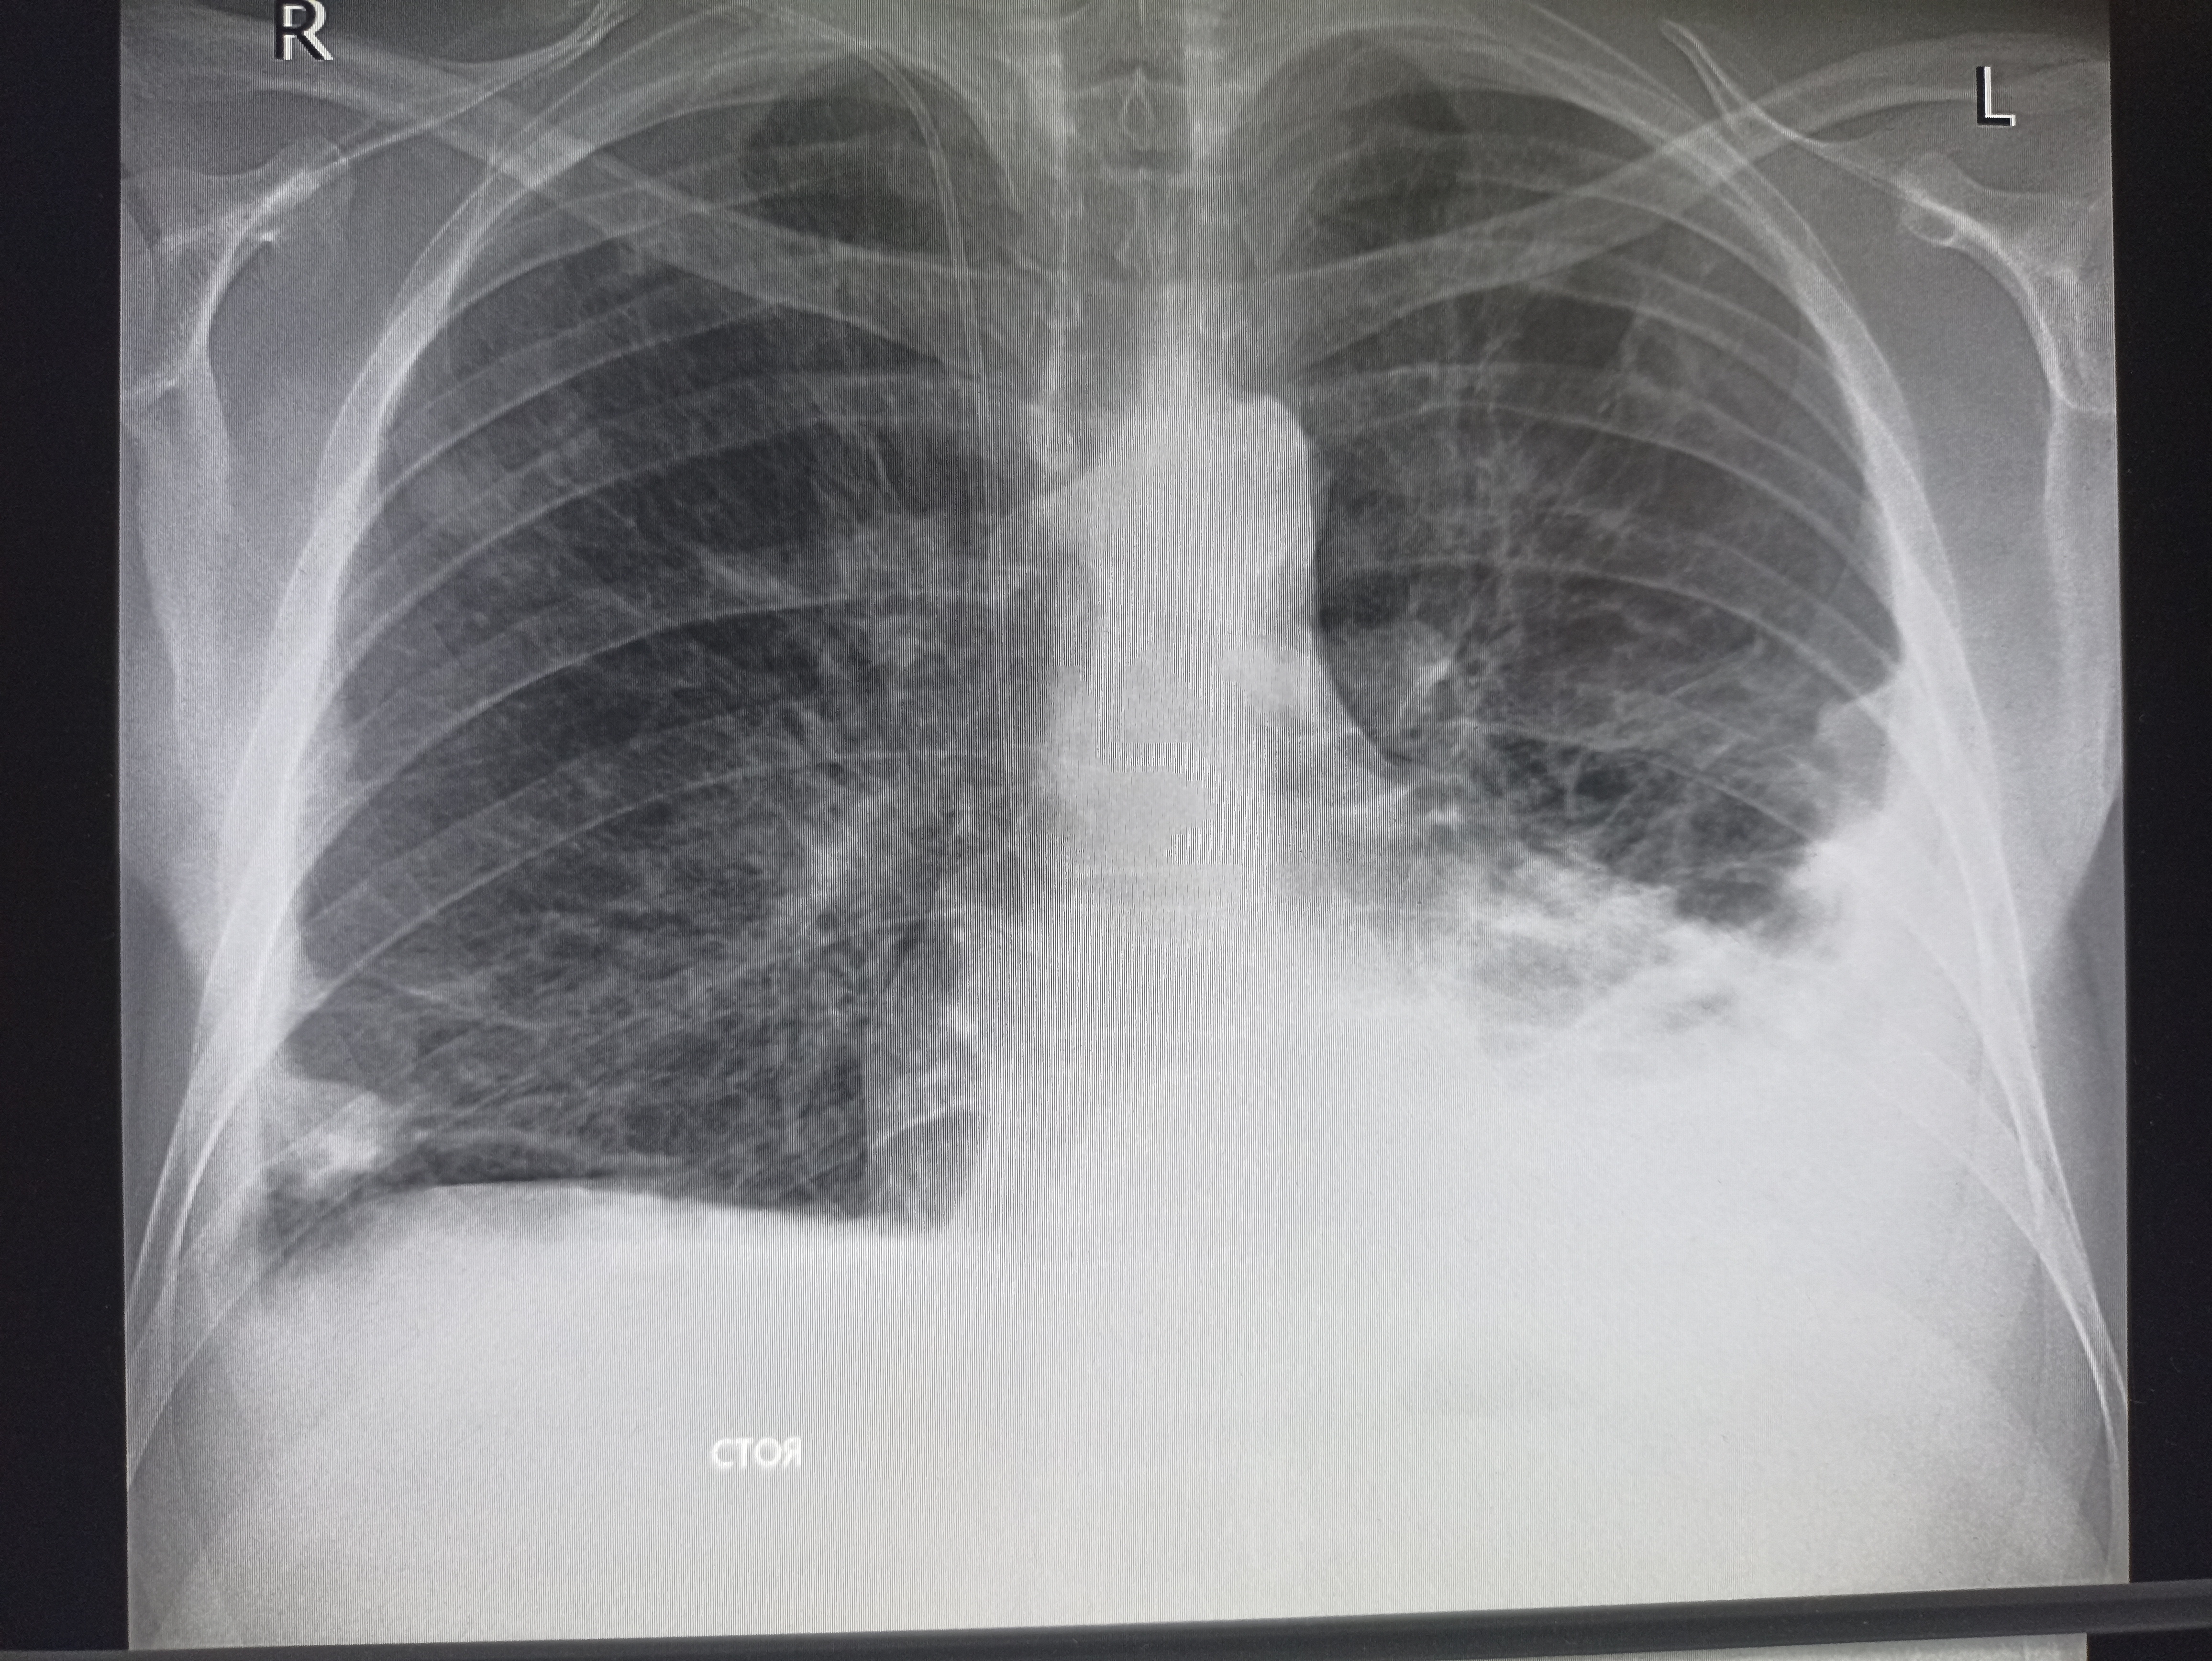

>>327474857

Бля то ли субтотальная пневмония, то ли осумкованный плеврит такой. всё нахуй забыл уже с рентгенологии

>>327475456

Тут просто гидроторакс, там недостаточность по большому кругу

>>327474923

Ателектаз слева?

Аноним 09/12/25 Втр 08:22:33 #42 №327475511

Хм, так понимаю увеличены сердце и магистральные сосуды, которые дают такую мощную тень?

Где пиздецома?

Аноним 09/12/25 Втр 08:27:51 #47 №327475609

>>327475506

И опухоль тож, там рак желудка первичный

Аноним 09/12/25 Втр 08:28:51 #48 №327475631

>>327475511

Сердце почти нк расширено, там рак с первичным очагом в желудке.